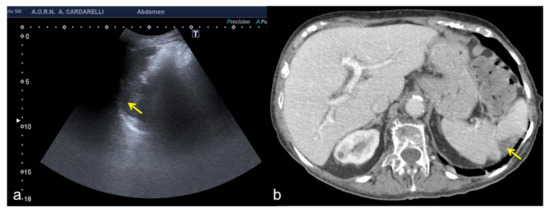

Figure 16. Coronal US scan of the left hypochondrium (a) shows a crescent-shaped hypoechoic area misinterpreted as hematoma (arrows) between the surface of the spleen and the left hemidiaphragm in a 25−year-old man investigated for trauma. On CT scan (b) it appears to be a hypertrophy of the left hepatic lobe with splenic kissing (circle).